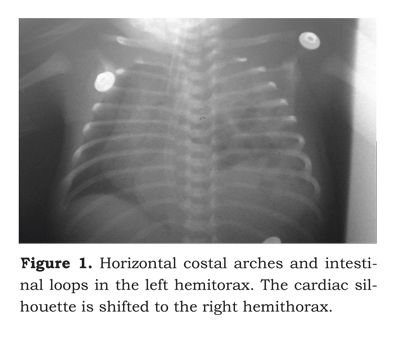

The chest X-ray showed intestinal loops in the left lung space up to the upper segment, with right mediastinal shift (figure 1).

The postnatal diagnosis is confirmed with a chest X-ray at birth, which may show intrathoracic intestinal loops, mediastinal shift, absence of, or decreased intestinal gas and the tip of a nasograstric tube inside the chest. A right-sided herniation requires a differential diagnosis with diaphragmatic eventration and lobe consolidation.